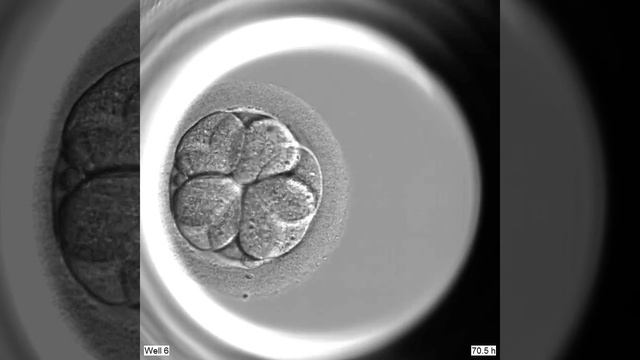

División celular en Embryoscope смотреть онлайн

00:28

División celular en Embryoscope